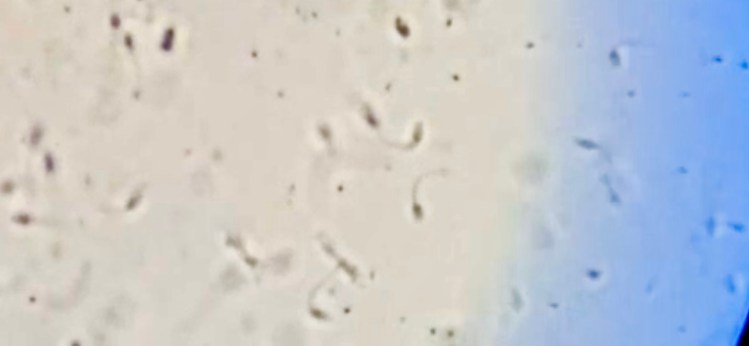

Dr. Kathryn Sharbrough of Charleston Equine Clinic, who has been treating this illness from the start, came yesterday to ultrasound the testicle to better ascertain what’s happening within. You can see from the ultrasound above that his testicle is rimmed by scar tissue varying from .5″ to an excess of 1″ thick. Moreover, the cells within the testicle appear abnormal, almost degenerative in nature, like fibrosis brought on by chronic inflammation and mineralization too.